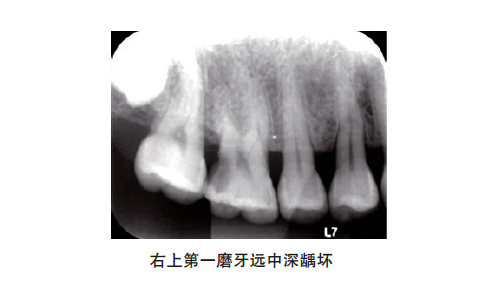

對于深齲患牙,建議治療前拍攝X線片了解髓腔結(jié)構(gòu)及其變化,著重觀察髓角位置,以及病損深度與髓腔的關(guān)系。這樣,在設(shè)計洞形時,可以避開髓角部位;在去除近髓的腐質(zhì)時,避免向髓腔方向加壓。